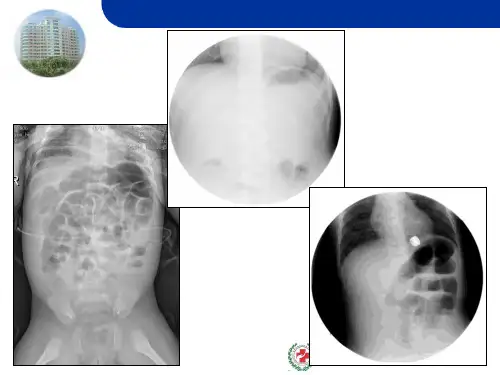

便血: 为肠套迭最重要症状之一。发病后4~12小时,就可出现 紫红色或“猪肝色”大便,并有粘液。直肠指诊指套上可染 血迹,有时可触到套迭之头部。

腹部包块:

在病儿安静或熟睡时,腹壁松弛情况下,在腹部可摸到 “腊肠样”的肿块,如为回盲型,则肿块多在右上腹部或腹 中部,表面光滑,稍可移动,腹痛发作时,肿块明显,肠鸣 音亢进,右下腹有“空虚感”。但在就诊较晚的病儿,由于 明显腹胀或腹膜炎存在而使肿块不易扪清